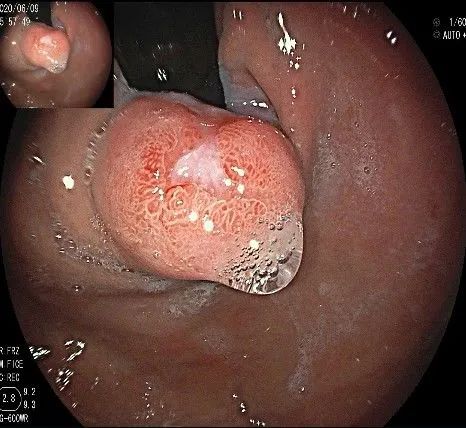

沿切开的边缘,从口侧开始向下进行粘膜下剥离,剥离的间隙是瘤体之上粘膜之下,期间反复进行粘膜下注射。

随着剥离的进行,瘤体与周围组织的关系越来越清晰。

此时瘤体基底部已暴露出来,起源于固有肌层。

这是最后的“根”部。

换用IT刀可以轻松剥离,又避免切入过深造成穿孔。

剥离接近完成,最后连接的薄层组织。